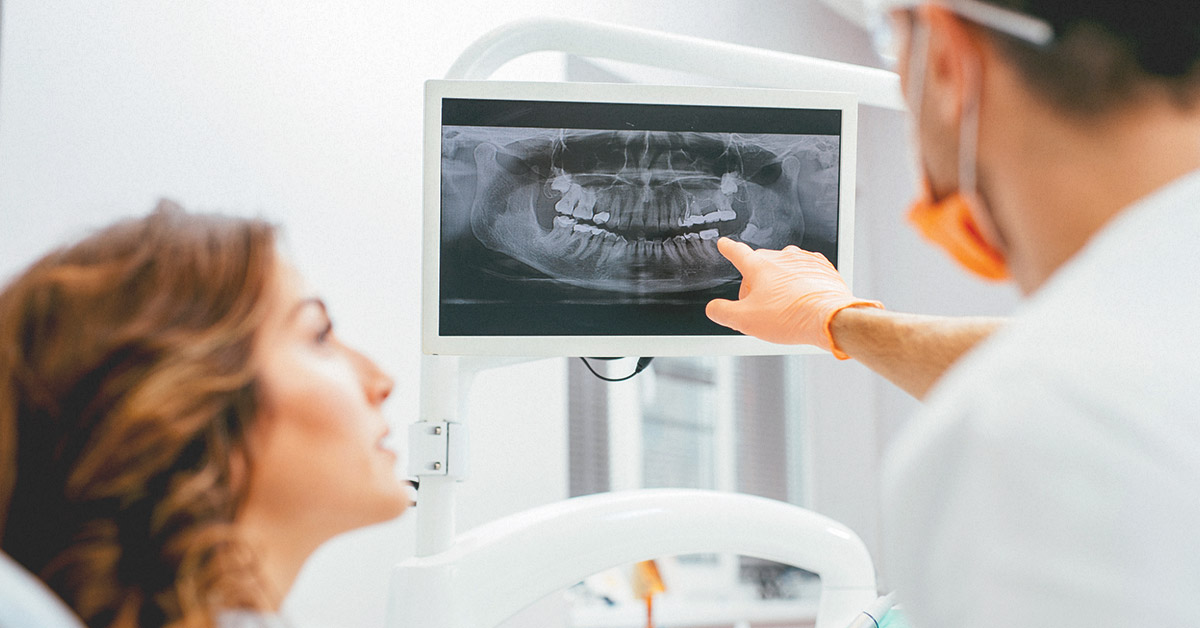

Планирование лечения зубов и его проведение сегодня не обходится без рентгенологических методов диагностики – прицельного снимка зуба, панорамного снимка зубочелюстной системы (ортопантомограммы) и компьютерной томографии. И сегодня мы хотим поговорить с Вами о панорамном снимке. Именно такое исследованиедля большинства стоматологов является «золотым стандартом» при «знакомстве» с пациентом – он необходим и для терапевта, и для хирурга, и для ортодонта.«Зачем же нужен панорамный снимок зубов? Где его можно сделать и сколько это будет стоить?» – это самые часто задаваемые вопросы пациентами, на которые мы хотим ответить в этой статье.Еще раз о том, что такое панорамный снимок зубов

На начальном этапе оценки состояния полости рта стоматолог обязательно назначает панорамный рентген-снимок.

Панорамный снимок (или ортопантомограмма) – это плоское двухмерное изображение челюстей, зубов, гайморовых пазух и даже височно-нижнечелюстного сустава. Поскольку поверхность челюстей изогнутая, на плоской рентгеновской плёнке снимок отображается неравномерно увеличенным в боковых и передних отделах челюстей – то есть слегка деформированым.